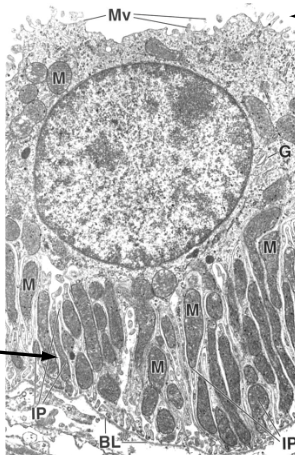

which convoluted tube has a brush border and abundant mitochondria?

PCT

Renal PCTs possess brush borders with a _______ to facilitate reabsorption; waste products are not actively removed, they are just not selected

glycocalyx

reabsorption is a 2 step process:

pump nutrient to ECM

uptake into capillaries

what is being actively reabsorbed into peritubular capillaries in PCT?

Na+

amino acids

sugars

peptides (by endocytosis)

what is being passively reabsorbed into peritubular capillaries in PCT?

water

Most reabsorption of filtered substances happens here, aided by abundant microvilli and glycocalyx on the apical surface, and basal transport to the extracellular matrix for uptake by peritubular capillaries